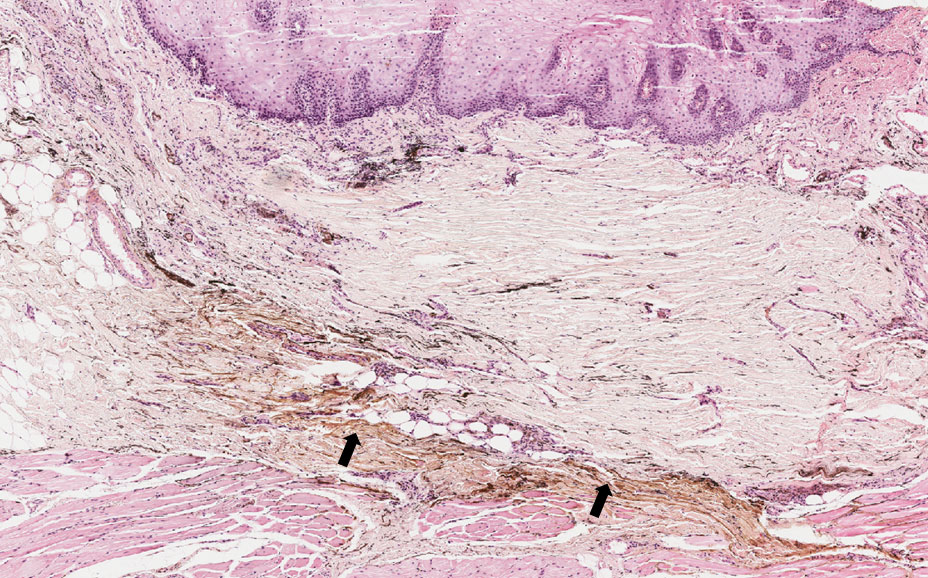

Mancha provocada pela inserção de partículas de amálgama no tecido conjuntivo.

Fragmento de mucosa bucal revestida por epitélio estratificado pavimentoso ceratinizado, onde podemos observar no tecido conjuntivo fragmentos sólidos, escuros, acastanhados e dispersos entre as fibras caracterizando fragmentos de amalgama (setas). Os sais de prata do amálgama tem afinidade com as fibras reticulares, especialmente aquelas que circundam os nervos e vasos.

Retenção de fragmentos de pigmento exógeno – amálgama de forma dispersa e reticular, acompanhando as fibras colágenas do tecido conjuntivo (setas).

Tatuagem por amálgama.